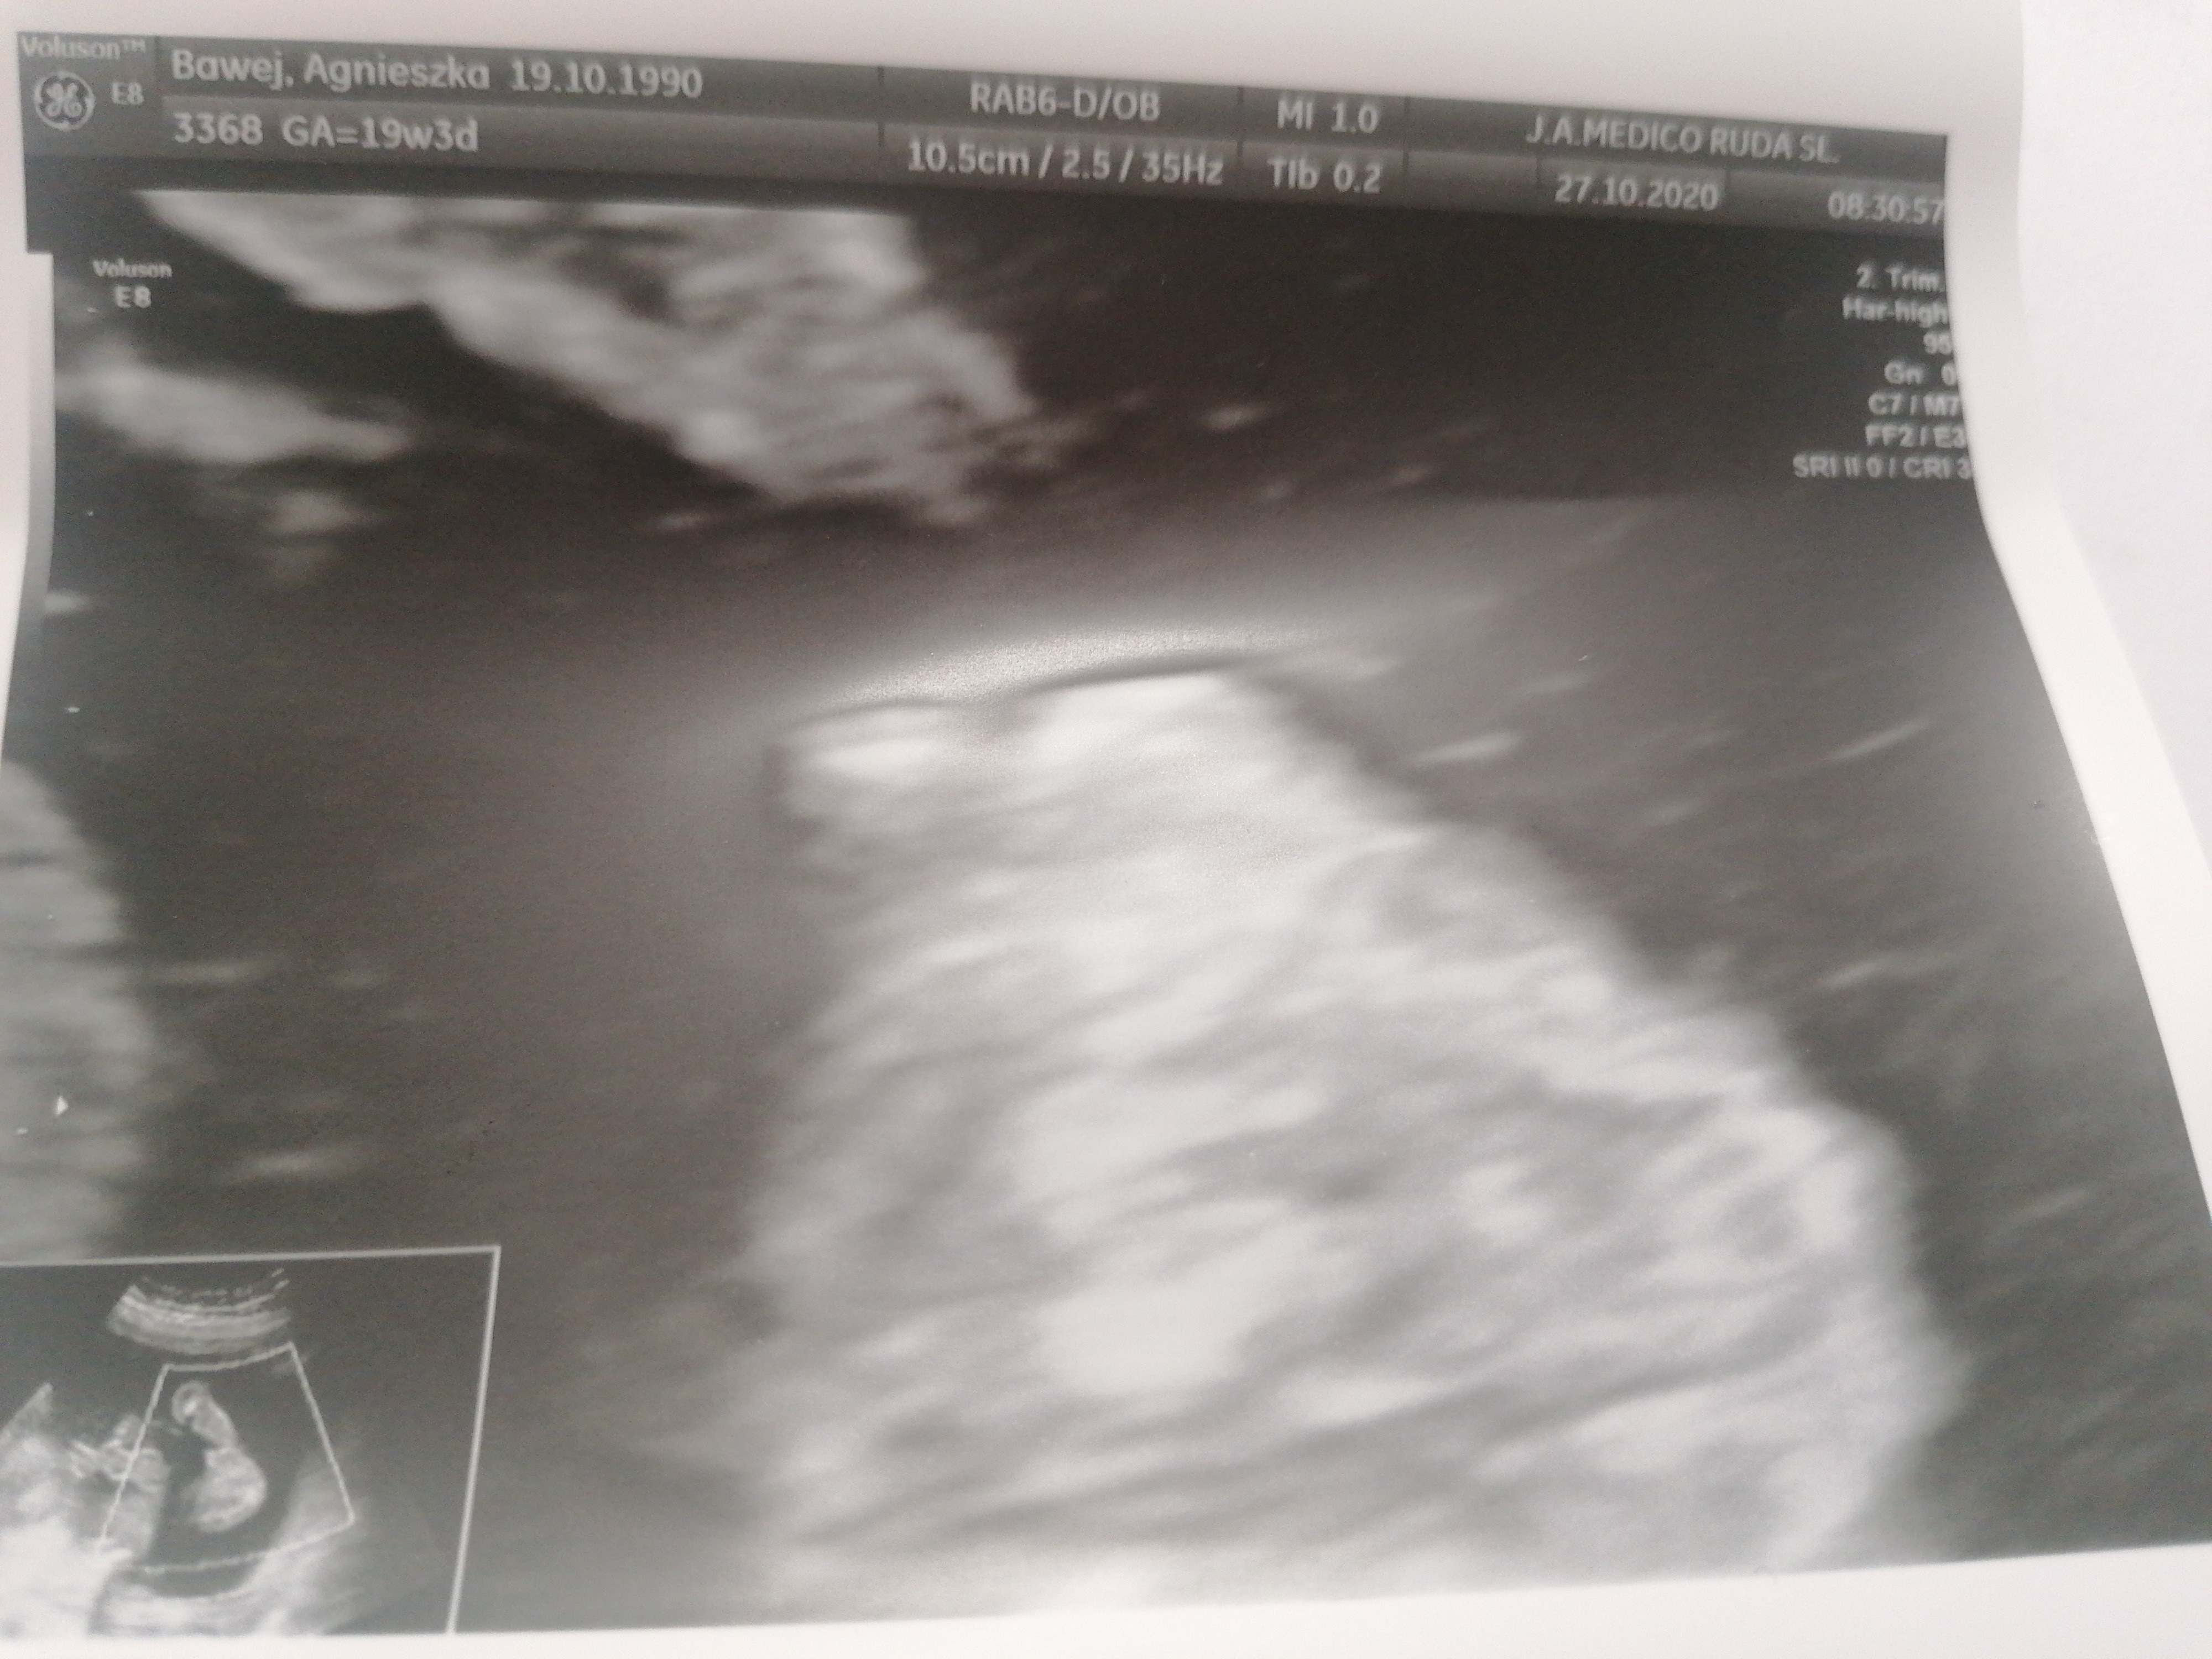

Czy na tym usg widac płeć dziecka

Witam lekarz nie chciał nic powiedzieć bo mówi że może się pomylić. Jak myślicie czy na tym zdjęciu usg już coś widać?

Widać chyba ślad wyrostka, ale niestety na jego podstawie ocenić płeć potrafi tylko dobry lekarz z dobrym sprzętem do USG.